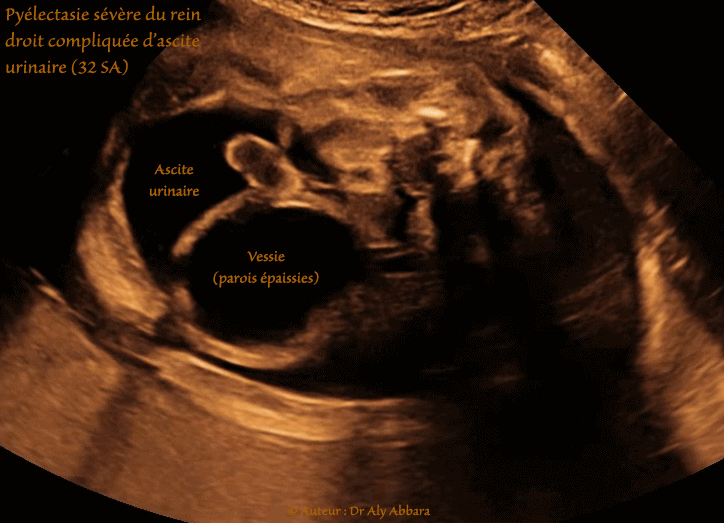

Vidéo et images échographiques (balayage axial) montrant une sévère pyélectasie (à 51 x 44 x 46 mm) puis la rupture de l'urinome avec la constitution d'une importante ascite urinaire.

Grossesse de 32 SA ; foetus du sexe masculin.

La vessie est en réplétion avec parois vésicales épaissies (de 4 à 5 mm).

Dans les pathologies obstructives sévères de l'arbre urinaire, l'urinome peut, sous l'effet de la surpression de fissurer le péritoine avoisinant pour laisser son contenu se vider dans de la cavité péritonéale entraînant la constitution d'une ascite urinaire.